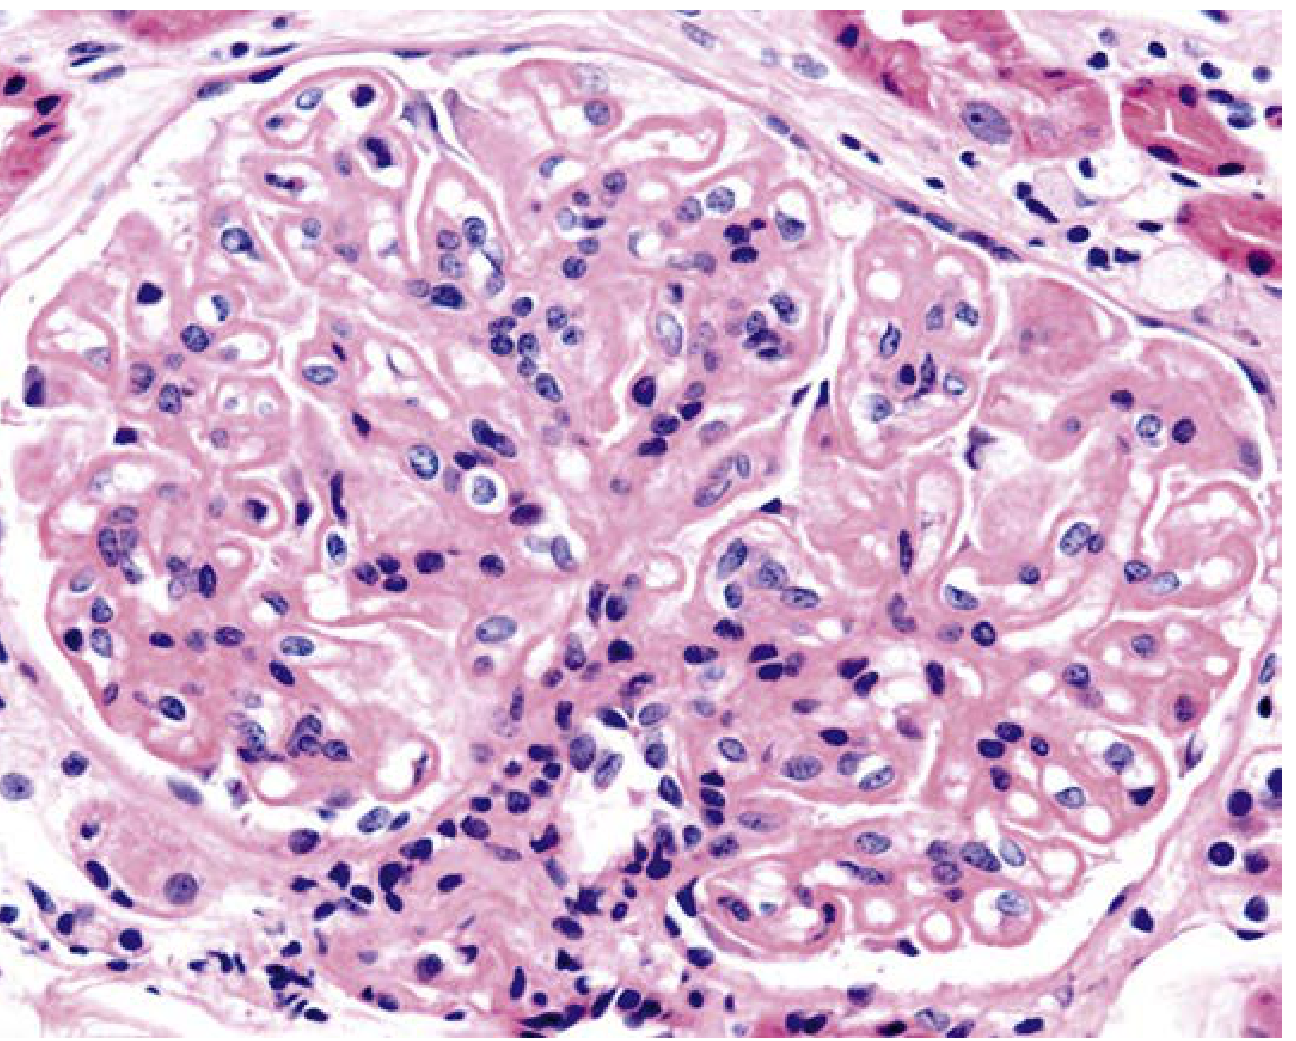

Class V histology (H&E, ×400) — spherical capillary wall thickening with mild mesangial hypercellularity:

Lupus nephritis Class V H&E